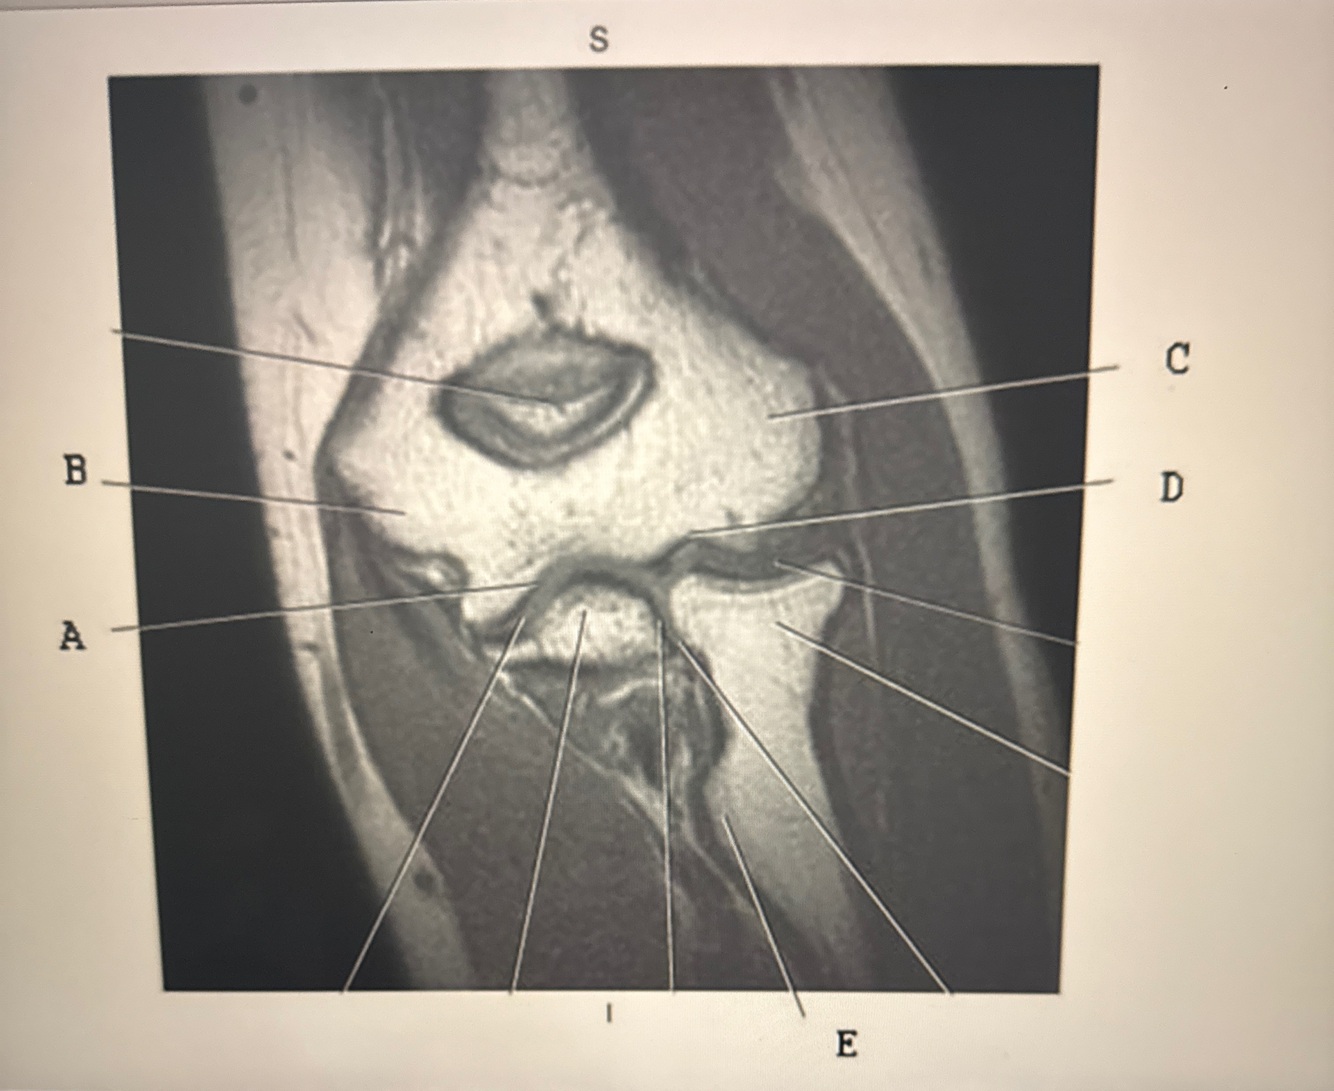

23

Q

Which line points to the annulus fibrosis?

A